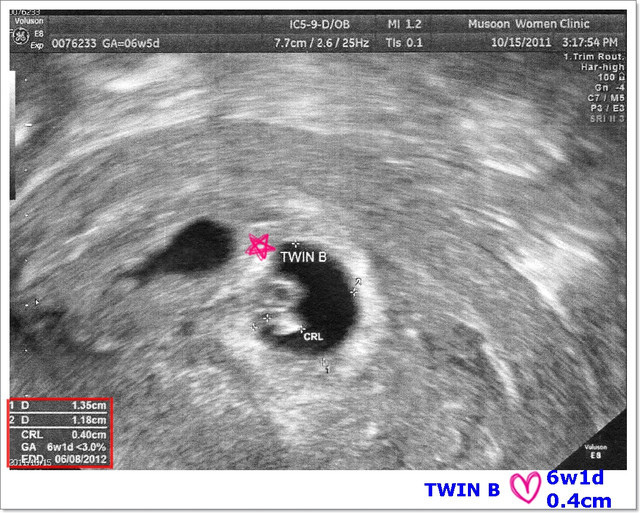

照著照著,突然在螢幕上看到寶寶身上有一個小亮點,隨著心跳一閃一閃的!

天啊~生命真的很神奇也!第一次看到寶寶們的心跳,這一刻我躺在診療室感動到眼眶泛紅>/////

有心跳代表一個生命的開始,我的身體裡有著三個心跳!這是上天賜給我們的小生命![]()

接著,超音波室居然出現很大聲的「咚咚~咚咚~咚咚~」!

我跟老公互相對看了一下,覺得不可思議了,

超音波師分別給我們聽了兩個寶寶的心跳,當下~我的心情真的很複雜>/////